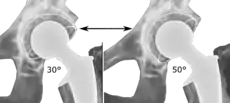

Post-operative projectional radiography is routinely performed to ensure proper configuration of hip prostheses.

The direction of the acetabular cup influences the range of motion of the leg, and also affects the risk of dislocation.[9] For this purpose, the acetabular inclination and the acetabular anteversion are measurements of cup angulation in the coronal plane and the sagittal plane, respectively.

Acetabular anteversion.[81] This parameter is calculated on a lateral radiograph as the angle between the transverse plane and a line going through the (anterior and posterior) margins of the acetabular cup.[81]

Acetabular anteversion.[81] This parameter is calculated on a lateral radiograph as the angle between the transverse plane and a line going through the (anterior and posterior) margins of the acetabular cup.[81] Acetabular anteversion is normally between 5 and 25°.[9] An anteversion below or above this range increases the risk of dislocation.[9] There is an intra-individual variability in this method because the pelvis may be tilted in various degrees in relation to the transverse plane.[9]

Acetabular anteversion is normally between 5 and 25°.[9] An anteversion below or above this range increases the risk of dislocation.[9] There is an intra-individual variability in this method because the pelvis may be tilted in various degrees in relation to the transverse plane.[9]